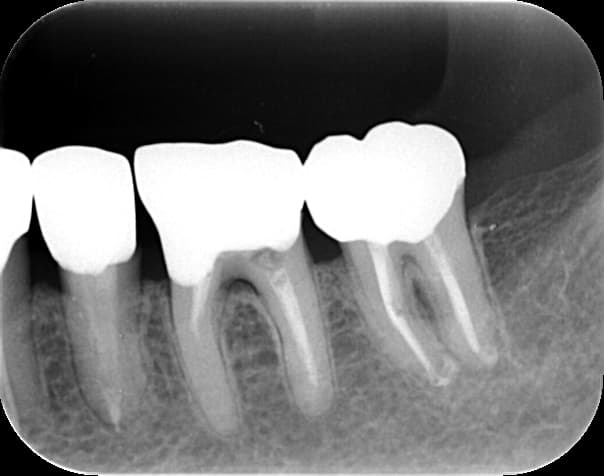

3. 矯正治療前に根管治療を済ませたほうがよい理由

矯正中は歯が動くため、弱っている歯や神経が炎症を起こしやすい時期です。特に、以下のような歯は矯正前に治療した方が安心です。

・大きな虫歯がある

・神経まで深い虫歯が近い

・すでに痛みを繰り返している

・歯髄の炎症が疑われる

・過去の治療が不十分

このような歯をそのまま矯正に進むと、矯正中に 「急に痛みが出る」「歯がしみる」「咬めない」 といったトラブルが発生しやすくなります。

矯正中は器具がついているため治療が難しくなり、治療計画全体が遅れるケースもあります。

そのため、矯正前に “怪しい歯は先に治療しておく” ことが、矯正期間をスムーズに進めるための重要な準備です。